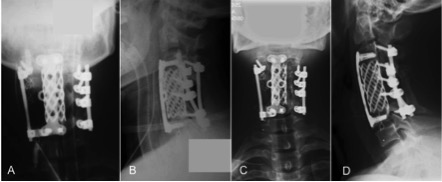

Osteosarcoma “tipo osteoblastoma” de columna cervical. A propósito de un caso. [Osteoblastoma like osteosarcoma of the cervical spine]